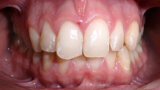

ClearCorrect treatment of crowding